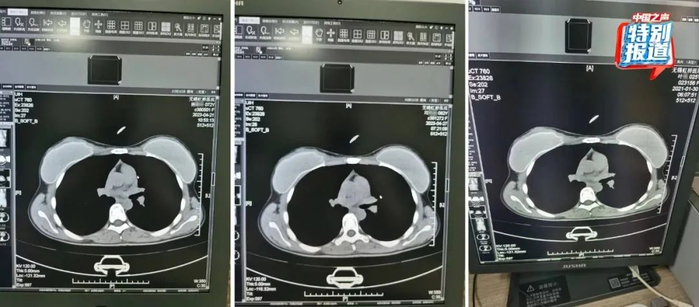

此外,该医生还反映医院存在多名患者CT影像高度相似的情况。

在被举报的病历中,杨某某(72岁)和邱某某(62岁)两位患者CT影像中的吊坠形状、大小和位置都基本一致。此外,2021年做过CT的25岁女性叶某的片子上,也有看起来极为相似的吊坠,肉眼看,三人的片子几乎一模一样。